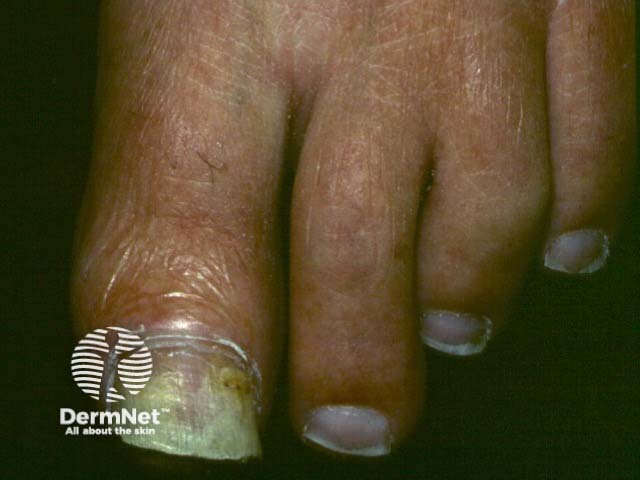

Non-dermatophyte mould onychomycosis (NDMO) is an opportunistic fungal nail infection (onychomycosis) caused by moulds.

Non-dermatophyte mould onychomycosis most often only affects one nail; toe nail involvement is 25 times more common than fingernail involvement.

The clinical sub-types of non-dermatophyte mould onychomycosis are similar to dermatophyte nail infections and include:

Paronychia is often present.

Infection may also lead to various nail colour changes depending on the infecting species. For example, infection with Aspergillus niger typically results in a black nail colour.